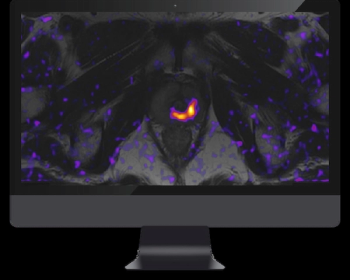

Offering comparable sensitivity to radiologists for detecting contralateral breast cancer on mammography images, an emerging adjunctive AI software may also facilitate earlier diagnosis, according to study findings presented at the at the 2024 American Society of Clinical Oncology (ASCO) Annual Meeting.